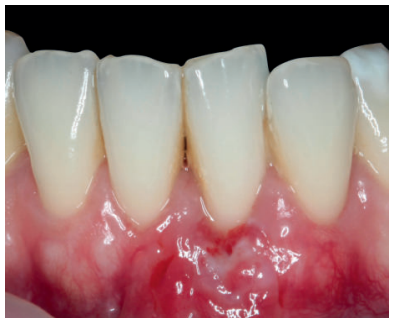

Una vez creado el lecho receptor, se procedió a la obtención de un ITC de la mucosa masticatoria palatina y a la sutura de dicho injerto mediante dos puntos colchoneros horizontales, uno situado en la parte mesial y otro en la parte distal del sobre. Para mayor adaptación y estabilización de las papilas se realizó un punto suspensorio cogiendo papila e ITC, mediante sutura de 6/0 no reabsorbible (Figura 3).

También, se realizó una sutura dentosuspendida para asegurar el injerto en posición apical, este punto se ancló en el periostio apical al injerto y suspendido alrededor de la cara lingual del diente con recesión mediante sutura de 5/0 reabsorbible. Se dejó cicatrizar por segunda intención en la base (zona de la vestibuloplastia).

Se realizó control a la semana de la intervención (Figura 4) y tras 15 días se retiró la sutura, observando la revascularización del injerto y la epitelización del área cruenta apical al sobre (Figura 5). Se realizó seguimiento al mes (Figura 6), a los 3 meses (Figura 7) y al año y medio del procedimiento (Figura 8).